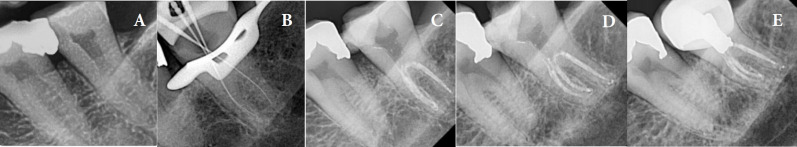

紧牙畸形是一种牙齿异常,其特征是在牙骨质-牙釉质交界处没有颈椎收缩,牙髓底顶端移位,牙髓腔扩大。由于其形态多变,根管孔深,根管系统复杂,因此对牙髓治疗提出了独特的挑战。本文报道了3例全身健康患者的高牛头牙症(牛头牙指数≈50),包括上颌第一磨牙、下颌第三磨牙和下颌第二前磨牙。锥束计算机断层扫描(CBCT)有助于诊断和治疗计划。根管治疗在牙科手术显微镜下进行,仔细探查,化学力学仪器使用旋转锉,5.25%次氯酸钠大量冲洗,温垂直封闭。12个月后,随访显示所有患者临床和影像学无症状,表明治疗成功。由于其解剖学的复杂性,剑齿虎症提出了重大的挑战。建议采用多方面的方法,包括CBCT、牙科手术显微镜、超声冲洗和温垂直封闭。这个系列的病例表明,先进的诊断辅助和细致的技术,甚至可以有效地管理高牛牙。

Taurodontism is a dental anomaly characterized by the absence of cervical constriction at the cemento-enamel junction, apical shifting of the pulpal floor, and an expanded pulp chamber. This condition presents unique challenges in endodontic diagnosis and treatment due to its variable morphology, deeply located orifices, and complex root canal system. This paper reports three cases of hypertaurodontism (Taurodont Index ≈ 50), including a maxillary first molar, mandibular third molar, and mandibular second premolar in systemically healthy patients. The identification and treatment planning were facilitated by cone-beam computed tomography (CBCT). Root canal therapy was performed under a dental operating microscope, with careful exploration, chemomechanical instrumentation using rotary files, copious irrigation with 5.25% sodium hypochlorite, and warm vertical obturation. Twelve months later, follow-up visits showed that all patients were clinically and radiographically asymptomatic, indicating successful outcomes. Taurodontism presents significant challenges due to its anatomical complexities. A multifaceted approach involving CBCT, dental operating microscopes, ultrasonic irrigation, and warm vertical obturation is recommended. This case series demonstrates that with advanced diagnostic aids and meticulous techniques, even hypertaurodontic teeth can be effectively managed.